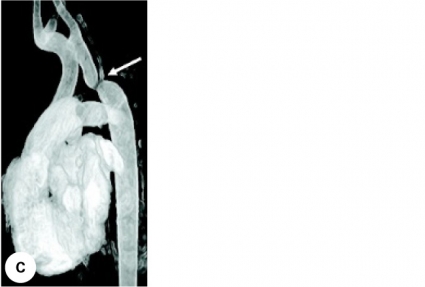

Figur 1 visar det medfödda hjärtfelet coarctatio aortae, framställt med angiokardiografi, ekokardiografi och MR.

MR har kommit som ett mycket värdefullt komplement till ekokardiografin och tillsammans nästan helt ersatt behovet av hjärtkateterisering med angiokardiografi. De flesta medfödda hjärtfel kan kartläggas fullständigt morfologiskt med MR-undersökning samtidigt som man kan göra hemodynamiska mätningar av flöden, gradienter, myokardfunktion mm. Begränsningar med MR-metoden på barn med medfödda hjärtfel är att den är dyr och tar lång tid att utföra. Att ta fram de bästa bildplanen och att göra flerdimensionella rekonstruktioner tar lång tid. Barn under skolåldern behöver vara sövda för att ligga stilla, och barn med magnetiska implantat, tex pacemaker, kan inte undersökas med MR. Allt snabbare datorer i MR-utrustningarna väntas i framtiden göra det möjligt att i realtid genomföra invasiva undersökningar och interventioner i MR-genomlysning. Om, och när, så blir möjligt kan barnkardiologen överge den radiologiska joniserande strålningen som använts sedan 1940-talet vid diagnostisk hjärtkateterisering.

De redan från början så viktiga radiologerna i teamen kring barn med medfödda hjärtfel har utvecklat nya metoder, som radiologisk datortomografi (DT) och givetvis den fantastiska icke-joniserande metoden magnetisk resonansundersökning (MR). DT-tekniken ger idag möjlighet till korta undersökningstider av barn i ingen eller lätt sedering. DT används vid utredning av vissa medfödda hjärtfel, särskilt kärlmissbildningar. Metoden begränsas dock av att barnen exponeras för stråldoser vars långsiktiga effekt på deras hälsa är oklar.